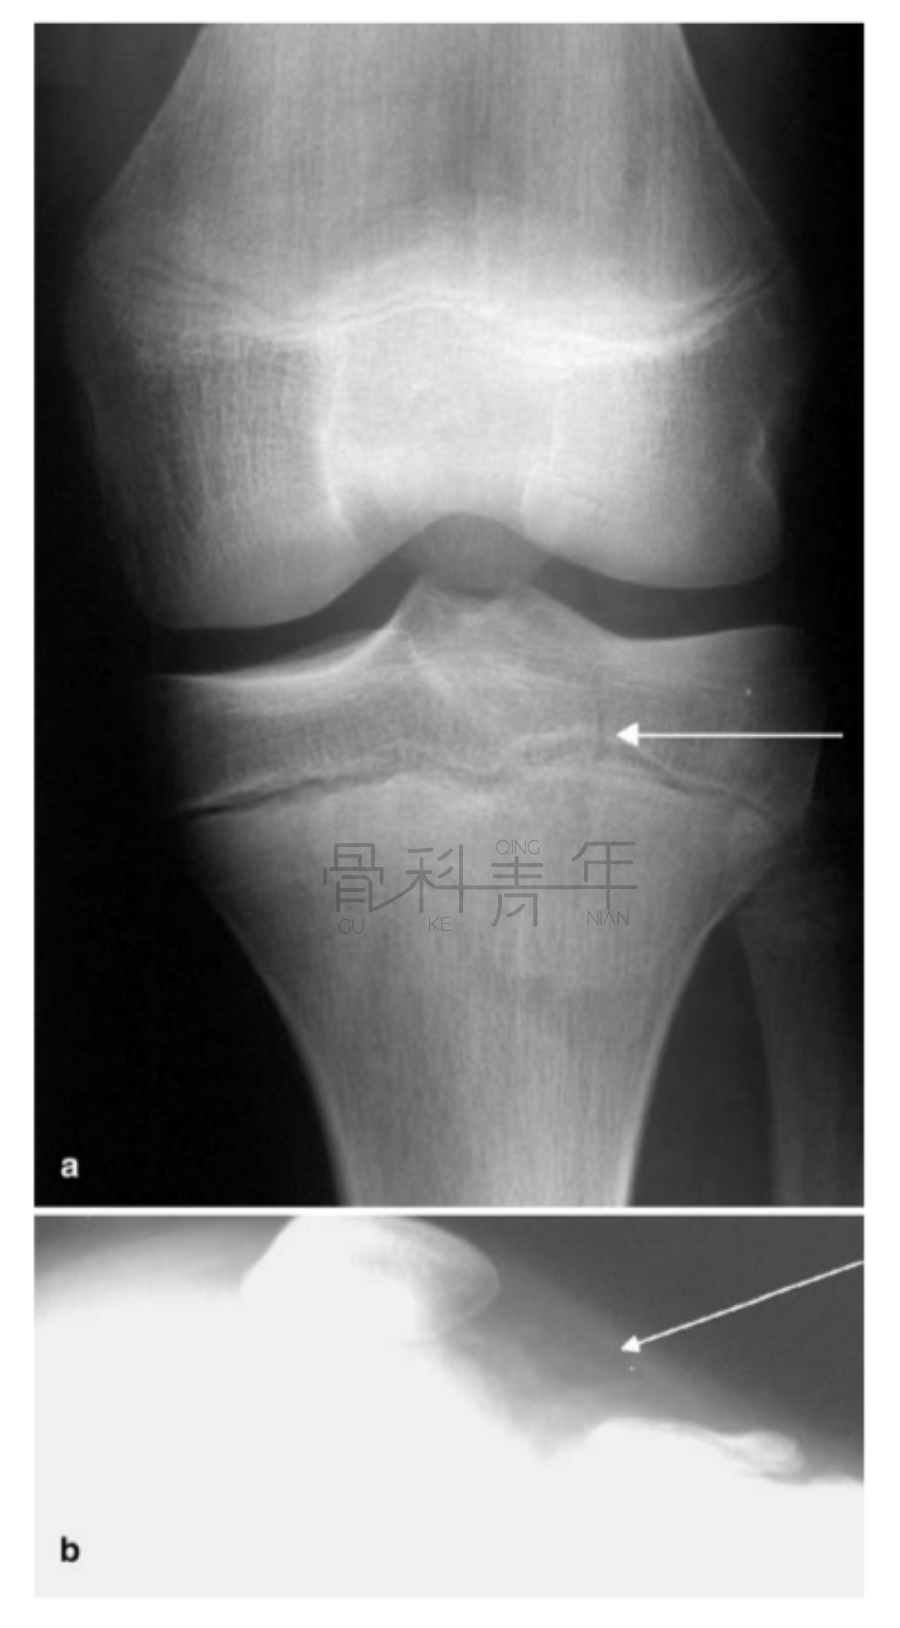

病例1在膝关节X线正位片上可见骨折间隙(a),侧位上可见明显关节积脂血症。